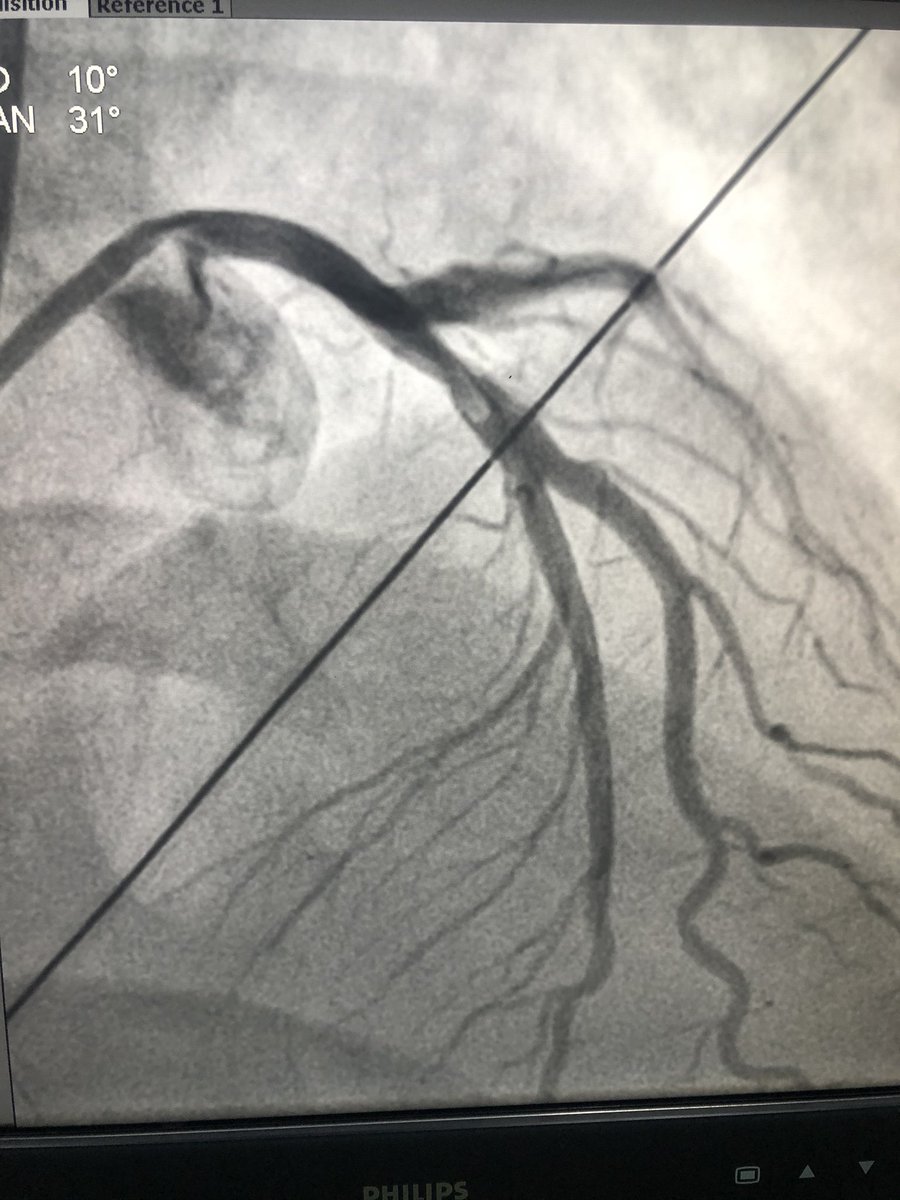

Proximal LAD had an ulcerated lesion too with thrombus - explains why the pt got so sick. How many times do you see a pt getting VT and getting intubated for RCA occlusion ? I guess here it's the LAD causing all the mayhem.